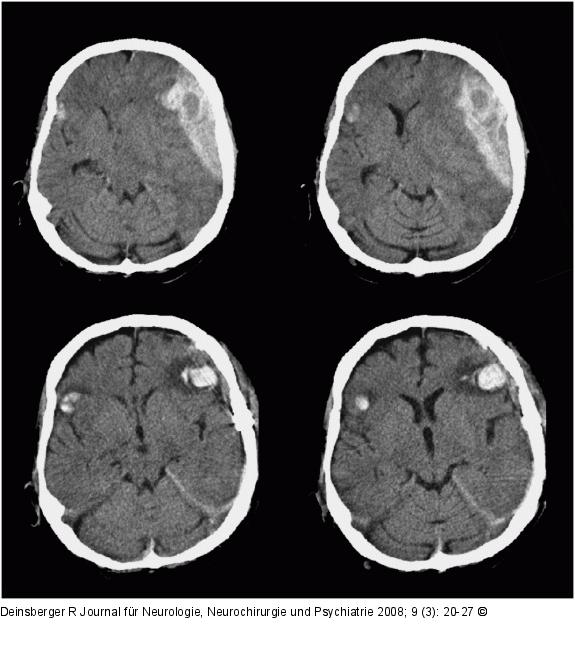

Abbildung 2: Kontusionsblutung Patient mit Zunahme der Kontusionsblutungen 24 Stunden nach Operation des Epiduralhämatoms |

Abbildung 2: Kontusionsblutung

Patient mit Zunahme der Kontusionsblutungen 24 Stunden nach Operation des Epiduralhämatoms |